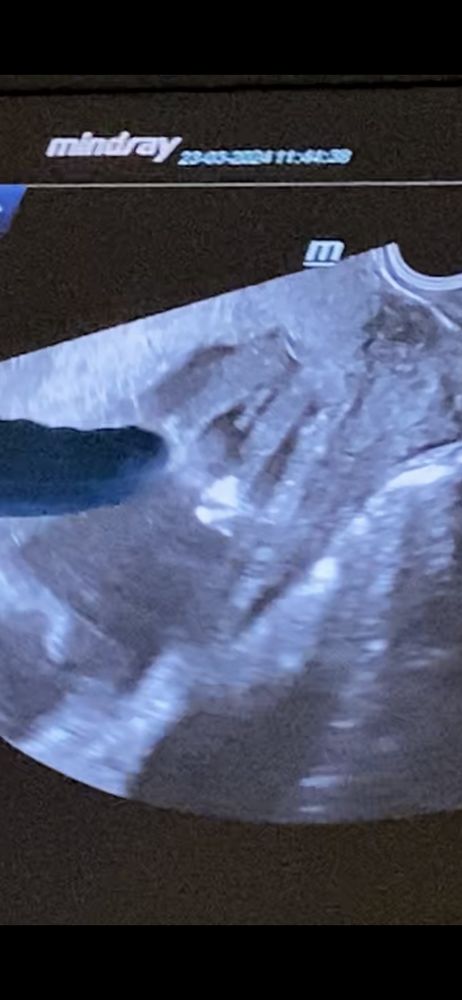

Вот есть ощущение, что на размытой третьей фото пуповина. А так девочка. Сходите к другому врачу, пусть со всех ракурсов покрутит

Таня, вот и я не пойму( в одних ракурсах как будто между ножек ничего не торчит, а в другом ракурсе торчит, но как будто не совсем очевидно , что писюн Изображение Изображение Изображение

Я, даже на 3 фото ?🙏🏻 я тоже на первых двух вижу девочку,но смущает другой ракурс, где врач сказала, что мальчик вероятнее всего..

Дарья , блин на 3 смущает да 😂

Дарья , кажется, врач пуповину перепутал с писей)